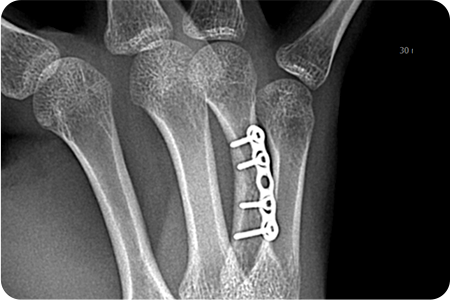

손 뼈 골절 수술

손은 작은 뼈들이 정교하게 연결되어 있어

골절 시 기능 손상이 크기 때문에,

정확한 정복과 고정이 중요합니다.